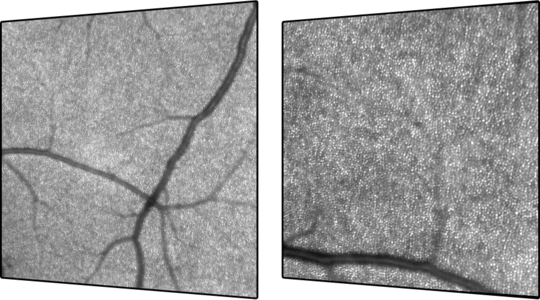

Retinal Mikroyapılar Yüksek Çözünürlükte!: SPECTRALIS® HMM, son derece yenilikçi bir büyütücü lens ve yazılımdan oluşur. Göz içi ışık saçılmasını azaltarak konfokal taramalı lazer oftalmoskopisinin (cSLO) oküler mikroyapıları görüntüleme yeteneğini zarifçe gösterir. Bu oküler mikroyapılar, kataraktı olan gözlerde dahi görülebilir. Konfokal tarama ile elde edilen görüntü kontrastı ve netliği, genellikle oftalmoskopi veya fundus fotoğrafçılığı kullanarak görülemeyen kritik tanısal ayrıntıları verir. Daha geniş görüş alanı sunan bir lens kullanılarak ilgili alan belirlendikten sonra, kullanıcı alanı daha da detaylı incelemek için yaklaşık 8° açıyla ve görüntüleri büyütülmüş olarak elde edebilir. Bu olasılık, belirli retina hastalıklarının ilerlemesi hakkında benzersiz bir bakış açısı sağlayabilir.